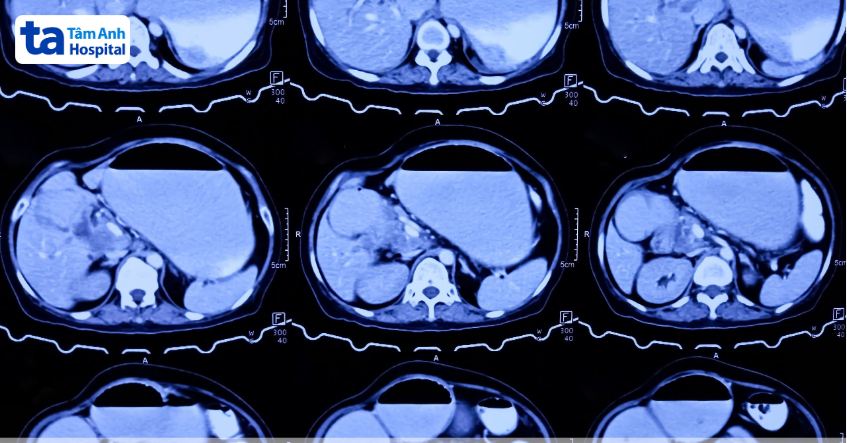

U mô đệm đường tiêu hóa (GIST) là khối u trung mô ác tính khá hiếm gặp ở đường tiêu hóa (chiếm 0,1 – 3%). U GIST có thể xuất hiện ở bất kỳ vị trí nào của của ống tiêu hóa, trong đó có khoảng 60-70% xuất hiện ở dạ dày, 20-30% ở tá tràng và ruột non, 5% ở tá tràng, thực quản và các bộ phận dưới chiếm 5%.

Những trường hợp GIST dạ dày không có triệu chứng, kích thước nhỏ dưới 2 cm thường chỉ cần theo dõi (cũng có quan điểm cắt bỏ ngay cả khi u dưới 2cm). Còn đa số cá các trường hợp còn lại, tùy thuộc vào mức độ tổn thương, vị trí, kích thước và xâm lấn tại chỗ của GIST dạ dày vào cơ quan lân cận, bác sĩ sẽ chỉ định phương pháp điều trị cắt bỏ phù hợp.

Phẫu thuật cắt bỏ GIST dạ dày là lựa chọn tối ưu trong điều trị GIST giúp lấy khối u triệt để. Phẫu thuật thường được chỉ định khi khối u trên 2cm, không có di căn. Phương pháp phẫu thuật cắt bỏ GIST dạ dày được thực hiện thông thường bằng phương pháp mổ mở truyền thống, phương pháp phẫu thuật xâm lấn tối thiểu hoặc cắt qua nội soi ống mềm (nội soi tiêu hóa).